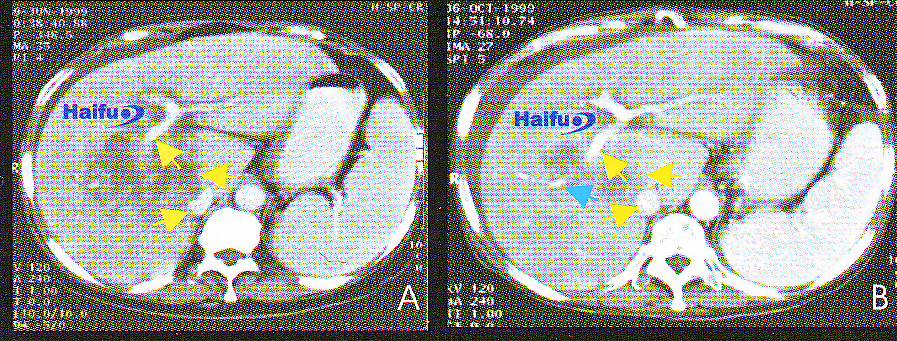

КТ-срезы с контрастированием 49-летнего пациента с гепатокарциномой, которому однократно проводился сеанс HIFU.

A) Перед лечением: визуализируется опухоль в левой доле печени (указана стрелкой) диаметром 4 см;

B) Через 3 месяца после HIFU; в опухоли отсутствует накопление контраста (стрелка);

C) Через 12 месяцев после HIFU; наблюдается уменьшение размеров опухоли, опухолевая ткань не контрастируется (стрелка);

D) Через 24 месяца после HIFU; отмечается прогрессивное уменьшение размеров опухоли (стрелка).

2. КТ-срезы с контрастированием 56-летнего пациента с гепатокарциномой в поздней стадии после однократного сеанса HIFU.

А) Перед HIFU пациенту проводилось три процедуры транскатетерной артериальной эмболизации, однако добиться контроля опухолевой прогрессии не удалось. Диаметр гепатокарциномы составлял 12 см. Опухоль инвазирует правую ветвь воротной вены (желтая стрелка), нижняя полая вена сдавлена (желтая стрелка), В брюшной полости определяется небольшое количество асцитической жидкости.

В) Четыре месяца после HIFU; отмечается регрессия опухоли (желтая стрелка), декомпрессия опухоли (желтая стрелка). В дистальном отделе воротной вены регистрируется кровоток (голубая стрелка), что означает реканализацию воротной вены.